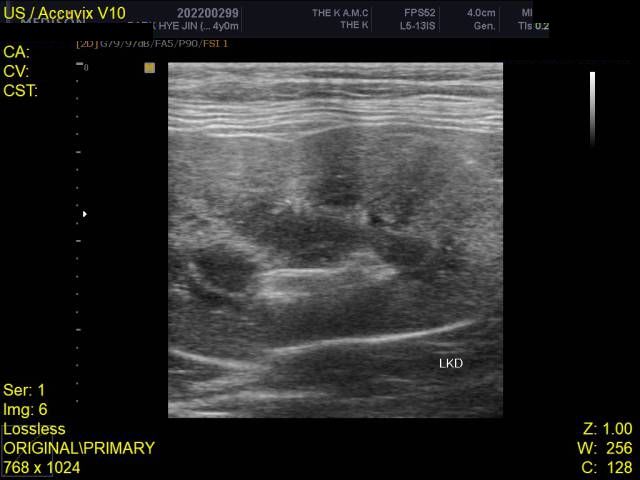

건강검진 때 받은 사진입니다

건강검진 받은 병원에서는 따로 소견을 주지 않으셨으나 지인이 이 사진을 보고

자신의 첫째 고양이가 진단 받았었던 HCM과 엑스레이 사진이 유사하다는 말을 들어서요

HCM의 경우 방사선 상으로는 완전히 진단하는 것이 어렵습니다.

진단을 하려면 영상전문 수의사로부터 심장초음파 소견을 듣는 것이 정확합니다.

HCM이 심할 경우 심장 모양이 valentine shape으로 보이기도 합니다. 아무래도 수의사 선생님이 이런 양상으로 HCM 가능성을 말씀하신 듯하니 심장초음파 진료가 가능한 병원 가셔서 검사 해보시기 바랍니다.

HCM의 진단의 golden standard 는 심장초음파 검사입니다. 하지만 첨부된 자료에는 심장 초음파 검사 결과가 없고

흉부 방사선 검사 또한 외측상이 결여되어 있어 자료로 판단할 수 없습니다.

주치의에게 요청하여 심장 초음파 검사를 진행해 보시기 바랍니다.